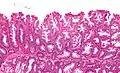

Histopathologie

La partie profonde des glandes est souvent élargie, a tendance à se diviser en deux ou trois branches et à s’horizontaliser, c'est-à-dire à se disposer parallèlement à la musculaire muqueuse et non pas perpendiculairement à elle, comme dans les polypes hyperplasiques conventionnels et les adénomes festonnés traditionnels.